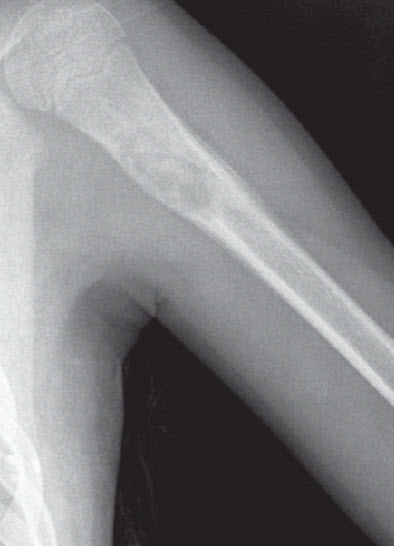

Anteroposterior and lateral views of the patient’s left humerus were ordered.

What do these radiographs show?

The radiographs show a centrally placed lytic lesion with lobulated contours and a well-defined transition zone in the proximal shaft of the humerus. An oblique pathological fracture runs through the cyst No other lesions are visible. A thick periosteal reaction on the medial aspect of the lytic lesion is also present; the peri osteal reaction is atypical in this case; however, the radiographs were obtained 10 days after the fall.

This is a unicameral, or simple, bone cyst. Many of the lesions in the differential diagnosis, including aneurysmal bone cyst, osteomyelitis, malignant lytic lesion (such as eosinophilic granuloma or bone metastasis), can be excluded on the basis of location. The location of simple bone cysts is usually the humeral head, ball of the foot, proximal femur, or proximal humerus or calcaneus.

A simple bone cyst may be an incidental finding. However, like this child, most patients present with a pathological fracture. The pathognomonic sign after a fracture is a fallen fragment in the most dependent portion of the cyst. Occasionally, a periosteal reaction can be seen. A simple bone cyst is a fluid-filled cavity lined with fibrous tissue. It is thought to result from venous outflow obstruction, which leads to an increased intraosseous pressure and a consequent stimulation of osteoclastic activity. This benign lesion usually develops within the first 2 decades of life. The cyst causes bone instability and sometimes may be associated with pathological fractures after relatively minor trauma.